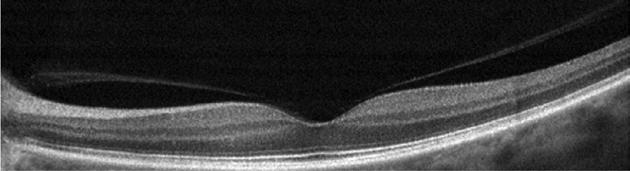

Type 2 MNV refers to the proliferation of new vessels originating from the choroid into the subretinal space. These vessels penetrate through the sub-RPE, making the subretinal portion the dominant component of the pathological process in Type 2 neovascularization. On FA, these lesions are usually “well-defined” as they present a well-demarcated area of hyperfluorescence in the early phase of the angiogram, followed by progressive dye pooling in the overlying subsensory retinal space during the late phase. (Figure 2)

Figure 2. Multimodal imaging of Type 2 macular neovascularization. Infrared reflectance (A) and fundus autofluorescence (B) revealing abnormalities of retinal pigment epithelium. Early and late phase of indocyanine green angiography (C and D) and fluorescein angiography (E and F) showing a well-defined neovascular network. Optical coherence tomography angiography (G) displaying the neovascular network. Optical coherence tomography (H) showing the neovascularization above the retinal pigment epithelium with disorganization of the overlying inner segment/outer segment junction.